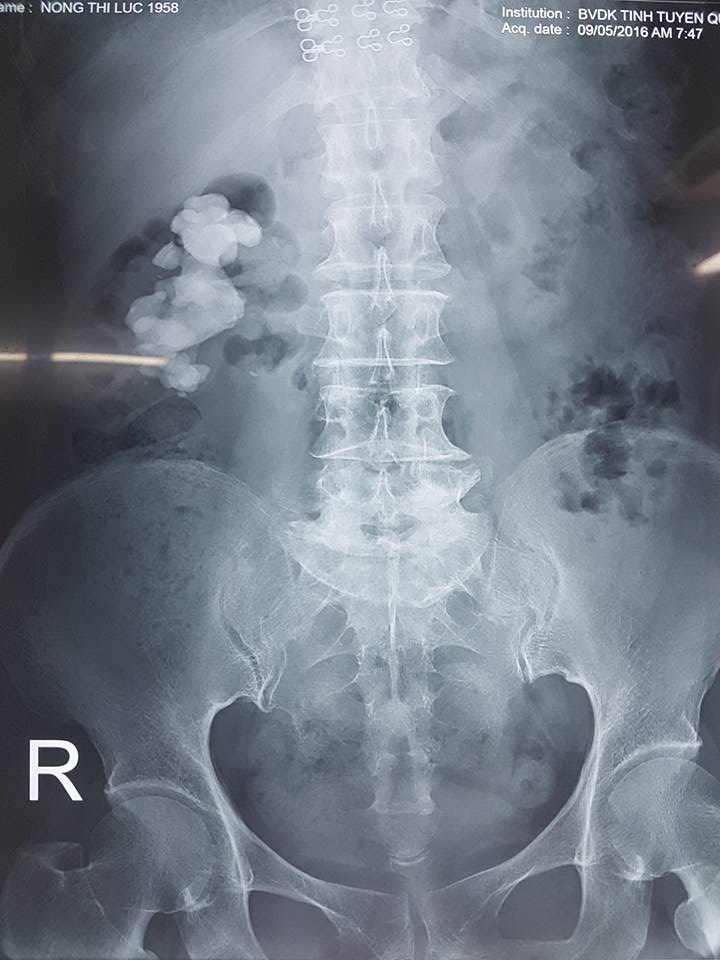

Hình ảnh sỏi thận trên phim chụp Xquang (ảnh BV) . |

Ths. Ma Ngọc Ba, Trưởng khoa Ngoại Thận – Tiết niệu người trực tiếp phẫu thuật cho bệnh nhân cho biết, qua các kết quả siêu âm và chụp X-Quang cho thấy, bệnh nhân bị sỏi thận bên phải đóng khuôn kín hết các đài thận, kích thước sỏi lớn nên sau khi hội chẩn các bác sỹ đã quyết định phẫu thuật mở cho bệnh nhân. Bệnh nhân có tiền sử tăng huyết áp và đã từng tán sỏi nội soi, bị viêm khớp và thoái hóa cột sống thắt lưng, dùng thuốc nam trên 10 năm và dùng nhiều loại thuốc khác nên ảnh hưởng đến chức năng thận.